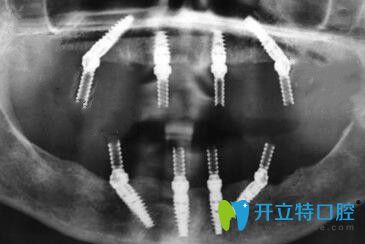

我在寧波恒美口腔做種植牙后的CT片

種植牙術后先戴的是臨時牙冠,但是不耽誤正常吃飯,只是比較硬的東西暫時不能啃~~~下面是2周后戴全瓷牙冠的照片▼,整個人看上去是不是年輕了很多呢!